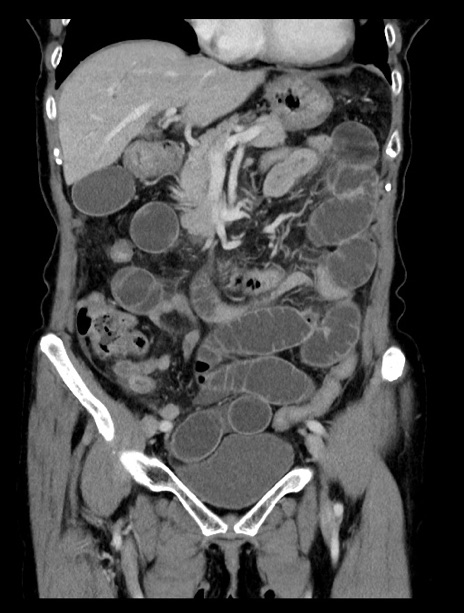

症例23(冠状断像)

【症例】70歳代女性

【主訴】下腹部痛・嘔吐

【現病歴】2日前より腹痛あり。昨日嘔吐あり。症状改善しないため来院。

【既往歴】胃GISTに対して胃部分切除後。

【身体所見】BT 37.1℃、BP 128/77mmHg、腹部:平坦・軟、下腹部に圧痛あり。

【データ】WBC 10200、CRP 0.31